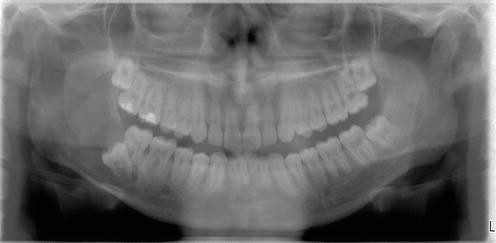

2012, after my jaw bone crumbled, then broke on the left side. Because the mandible has a faster remodeling rate compared to other bones in the body, it is more affected by the effects of these drugs. The cancer cells are bone cells that have become cancerous. Survival varies with each type of bone cancer.